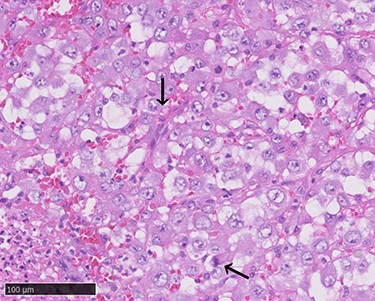

Haemorrhagic masses in the oral cavity. These were identified on the hard palate (A) and the left lower gingiva (arrow) (B). Two weeks after initial presentation (C). Spreading to the upper gingiva, maxillary bone and maxillary sinus (arrow; after resection) (D).

A 70-year-old Japanese woman was referred to our department. Her medical history indicated surgery, radiation therapy and intravascular treatment for AVM in her right upper limb since she was 17 years old (Fig. 1). One month before initial presentation, she noticed frequent haemorrhagic masses in her oral cavity. She complained of general malaise and loss of appetite. The masses bled readily upon scraping the hard palate (Fig. 2A). Similar masses were found on her left lower gingiva (Fig. 2B). Routine blood tests revealed normocytic normochromic anaemia of 4.6 g/dl, while no platelet or coagulation abnormalities were found. Open incisional biopsy under general anaesthesia was performed after conservative management, including blood transfusion, nutrition and oral care. The masses had grown rapidly and covered the hard palate and had spread to the upper gingiva, maxillary bone and maxillary sinus (Fig. 2C and D). The specimen consisted of bloody, dark-red and partially sponge-like lesions. Histologically, necrosis and haemorrhage were evident. In areas where viable cells were present, atypical, vascular endothelial cells with pleomorphic nuclei formed a solid lesion or a network to form a narrow lumen filled with blood cells (Fig. 3). Immunohistochemical staining was positive for CD31, CK (AE1 + 3), ERG, D2–40 and CK (CAM 5.2) and negative for CD34, FactorVIII, αSMA, MyoD1, Desmin, Myogenin, S100, HMB45, MelanA, CK (5/6), p63, p40 and EMA. MIB-1 staining showed a proliferation index as high as 50%. These pathohistological findings revealed the tumour as AS (FNCLCC Histological Grade 3).

Positron emission tomography–computed tomography (CT) revealed high fluorodeoxyglucose (FDG) accumulation in her oral cavity and right shoulder in accordance with the location of the AVM (Fig. 4). High accumulation was also evident in her left lung, lumbar spine, piriformis and lymph nodes, suggesting multiple metastases. We diagnosed the masses in the oral cavity as metastatic AS, with the primary tumour located in the right shoulder, where the massive AVM was suspected to have malignantly transformed. The patient desired the best supportive care and declined additional treatments such as radiotherapy and chemotherapy. She died 4 months after initially noticing the intraoral masses. An autopsy was not performed.